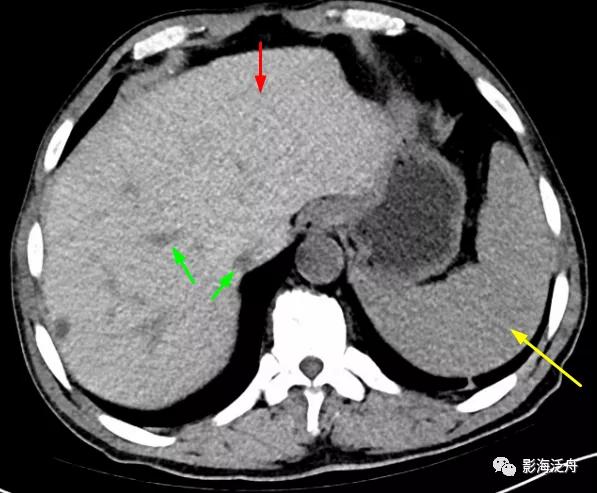

老年男性患者,因重度贫血就诊。

CT平扫上可见肝实质密度弥漫性增高,且明显高于同层面脾实质密度(黄箭),肝内血管呈较为明显的低密度改变(绿箭)。肝实质CT值75HU、脾实质CT值50HU。

同时需要注意的是肝实质密度增高≠肝内铁沉积,肝实质密度增高还见于结节病、Wilson病以及服用胺碘酮、甲氨蝶呤药物的患者。通常而言,肝实质密度在45~65HU之间,一般CT值大于或接近75HU可提示肝实质密度异常增高。